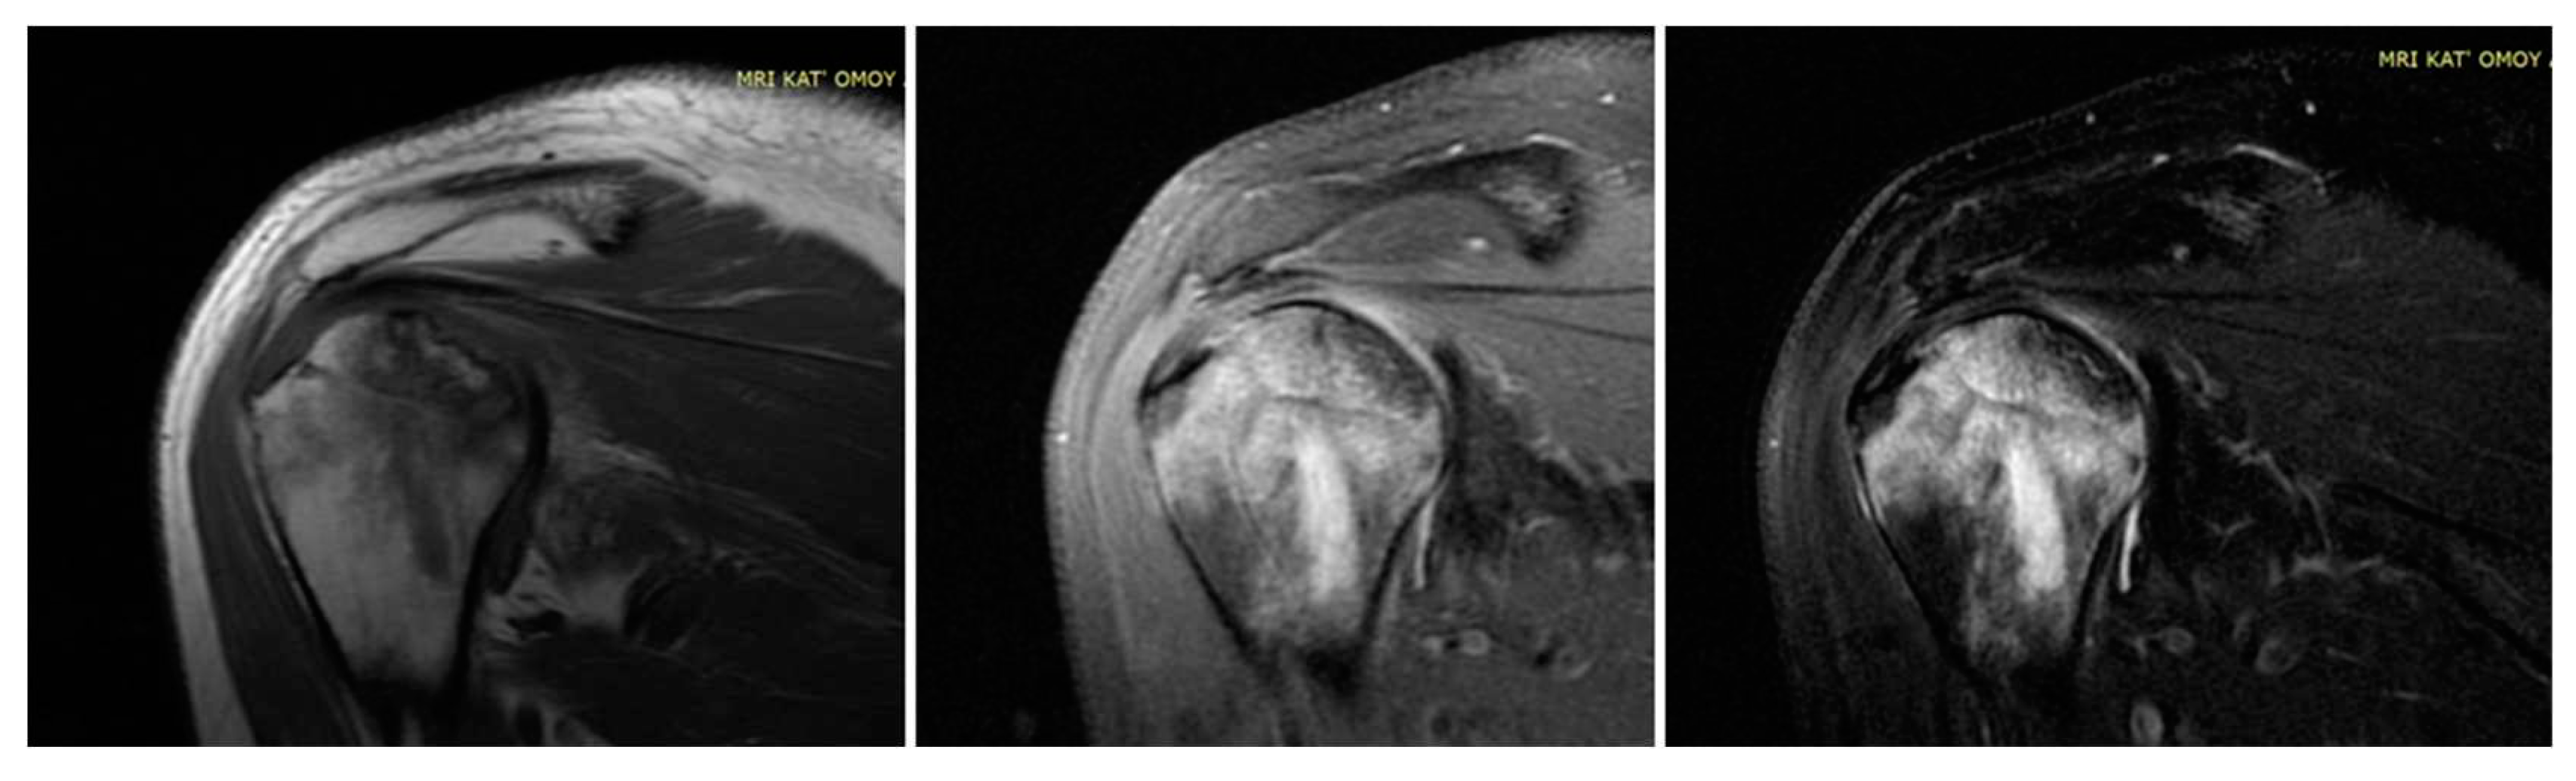

Figure 1. MRI of bilateral avascular necrosis of the hip after Covid-19 infection and treatment in ICU unit of our department.